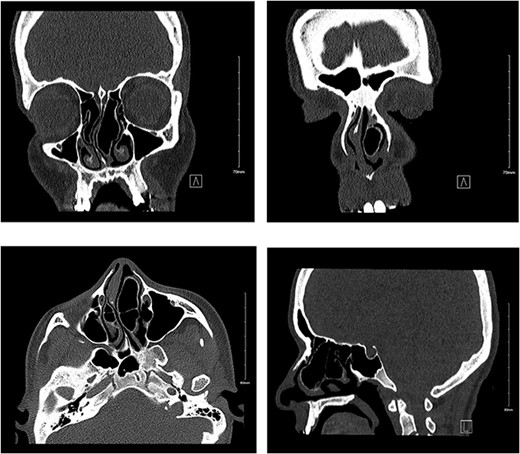

A 22-year-old female presented to our otolaryngology clinic with 3-year long complaints of bilateral alternating nasal obstruction and congestion more to the right side, associated with a mild to moderate intermittent, throbbing frontal headache and hyposmia. The patient’s quality of life was also affected due to sleep disturbance and mouth breathing. She denied any rhinorrhea, otorrhea, or otalgia. Patient is surgically and medically free. Upon examination, the patient had a severely deviated nasal septum to the right side, and bilateral enlarged turbinates with the left concha reaching to the nasal floor resembling polyp grade 4. For further evaluation, a non-contrast computed tomography (CT) of paranasal sinuses was performed. It revealed a right-sided deviated nasal septum with bilateral CB resulting in significant narrowing of the nasal cavity, with patent ostiomeatal complexes (Fig. 1). The option for surgical intervention was offered and explained to the patient, and the risks and benefits of the procedure were discussed thoroughly. Surgery was proceeded following patient’s approval. Under general anesthesia, the examination of the nose was performed using an endoscope and monitoring system, it showed a large left-sided CB extending through the nasal cavity reaching the nasal floor, right-sided CB reaching to the inferior turbinate, and a severely deviated nasal septum to the right side. Surgery started first with resection of the lateral part of the concha bullosa with the aid of turbinectomy scissor. Lower aspect of the medial part extending to the nasal floor was trimmed. After that, septoplasty was performed. Right CB was identified, the size was prominent reaching the inferior turbinate, it was removed with the same technique addressed earlier. Then bilateral turbinoplasty was performed. The patient tolerated the procedure and made an uneventful postoperative recovery. She was discharged in a stable condition with analgesia and hypertonic nasal saline irrigation. The patient was seen post-operatively and reported no active complaints, the nasal obstruction improved, no more sleep disturbance and headache free. However, the patient was still hyposmic. Endoscopic examination showed patent nasal cavity.

Non-contrast CT showing bilateral pnuematized concha bullosa, more prominent on the left pushing the nasal septum to the right side in coronal (a, b), axial (c), and sagittal (d) views.